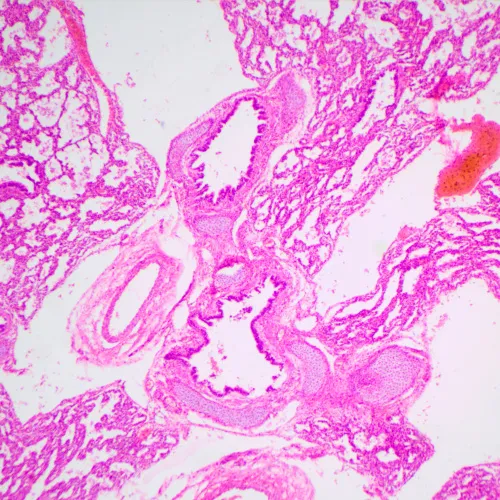

MAGUS Bio 240T ist ein kleines biologisches Mikroskop für Ausbildung und Forschung. Es ist für die Arbeit mit transparenten und transluzenten Proben biologischen Ursprungs im Hellfeldverfahren konzipiert. Das Mikroskop verfügt über einen codierten Objektivrevolver, der die gewählte Lichtintensität für jedes Objektiv beibehält, und ein LCD-Display, das die Betriebsparameter anzeigt.

• Arbeitet mit transparenten und transluzenten biologischen Präparaten im Hellfeldverfahren